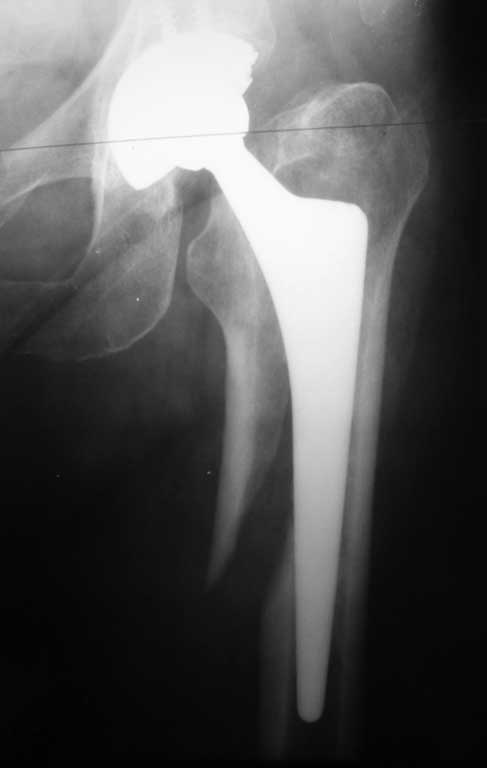

Уважаемые коллеги. Помогите определиться с тактикой лечения при перипротезном переломе бедра. Женщина 58 лет, ранее (в марте 2010г.) оперирована в нашем отделении по поводу перелома шейки бедра. Выполнено эндопротезирование сустава бесцементным протезом Зиммер (чашка Трилоджи и ножка Споторно). До получения последней травмы пациентка чувствовала себя хорошо: ходила не хромая , болей не было. 28.12.11 упала на улице. На рентгенограммах имеется перипротезный перелом бедра в верхней трети, проседание ножки протеза. Помогите с выбором тактики лечения. Наше мнение : ревизовать ножку на более длинную, предварительно выполнить остеосинтез бедра серкляжами. Вот только какую ножку выбрать: цементную или безцементную, Вагнера или Гелио (биомет) или длинную цементную ножку Экзетер(Страйкер). Всем спасибо.Всех с наступающим Новым Годом!!!

Уважаемый Сергей, нужна ножка Вагнера, а уже к ней Вы фиксируете фрагменты проксимального отдела серкляжами, так проще и надежней.

Уважаемый Сергей, необходима замена ножки на ножку типа Вагнера 190 или 225 мм, а фрагменты проксимального отдела фиксируете серкляжами. Это обычная практика в нашей клинике